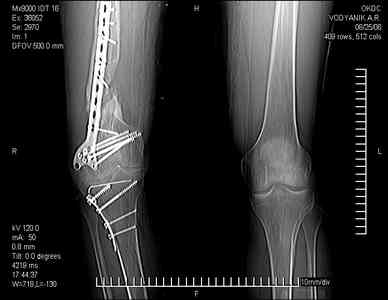

Уважаемые коллеги, В ортопедическое отделение обратился пациент: мужчина 47 лет, который в течение 4-х лет дважды получил травму костей, образующих правый коленный сустав.

В 2002 v внутрисуставной оскольчатый перелом проксимального метаэпифиза правой большеберцовой кости; в 2005 v внутрисуставной оскольчатый перелом дистального метаэпифиза правой бедренной кости.

В обоих случаях в разных лечебных учреждениях проводилось оперативное лечение переломов. При осмотре в отделении на основании результатов клинического осмотра и данных визуальных методов обследования поставлен диагноз: тугой ложный сустав дистальной трети правой бедренной кости, состояние после накостного остеосинтеза перелома типа 33-В2.2 ; несросшийся перелом надколенника; неправильно сросшийся перелом латерального мыщелка правой большеберцовой кости, состояние после металлоостеосинтеза перелома 41-В2.2; сочетанная осевая деформация правой ноги: варусная деформация правого бедра, вальгусная деформация правой голени; посттравматический артроз коленного сустава 4 ст по Kellgren-Lowrence; выраженное нарушение функции ходьбы и опоры.

Внешний вид ноги больного, данные рентгенографического обследования и избирательно выделенные компьютерные томограммы приведены в приложении. В именах КТ использовано кодирование уровня по АО, т.е. _41, например, означает проксимальную треть голени. В отделении намечен v очень предварительно v следующий план лечения: